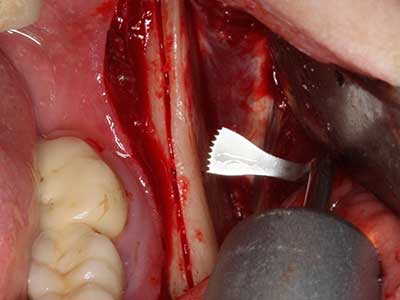

En la extracción de bloques óseos la piezocirugía también presenta ventajas adicionales: Además de la alta precisión en la osteotomía que ya se ha descrito antes, se ha comprobado que el uso de los delgados insertos de sierra resulta especialmente cuidadosas con el hueso. Frente a esto, sobre todo cuando se usan las fresas de Lindemann, cabe esperar pérdidas en la extracción significativamente más altas debido al mayor grosor de la parte frontal del cabezal (Lakshmiganthan, Gokulanathan et al. 2012). La separación basal que se necesita en particular en los injertos de bloque extraídos de forma retromolar se ve facilitada mediante sierras perpendiculares especialmente previstas a tal fin, lo que permite considerar que la cirugía piezoeléctrica es un procedimiento preciso y seguro para la obtención de bloques de hueso en el área retromolar (Happe 2007) (fig. 1-12).

Si es preciso realizar intervenciones quirúrgicas en las que el hueso está en contacto directo con estructuras sensibles, como son los vasos sanguíneos o los nervios, los instrumentos rotativos presentan un enorme potencial de provocar lesiones iatrogénicas. Así, precisamente en la representación de nervios después de una lesión iatrogénica, o en el transcurso de la lateralización de un nervio para resecciones, reconstrucciones o incorporación de implantes, los equipos piezoeléctricos pueden resultar muy útiles para preparar la tapa ósea y retirar las partes de tejido duro cercanas al nervio (fig. 17-20). Por lo general, un ligero contacto del cordón nervioso con el inserto piezoeléctrico no tiene consecuencia alguna; ahora bien, un procedimiento poco cuidadoso con movimientos tipo sierra o piezas de trabajo sobre la base ósea aún existente puede provocar lesiones nerviosas temporales o incluso permanentes. Con todo, el riesgo de sufrir una lesión de este tipo se considera significativamente inferior que en los casos en los que se utilizan sierras y fresas (Pereira, Gealh et al. 2014).